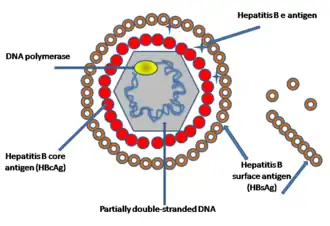

Viral hepatitis is primarily diagnosed through blood tests for levels of viral antigens (such as the hepatitis B surface or core antigen), anti-viral antibodies (such as the anti-hepatitis B surface antibody or anti-hepatitis A antibody), or viral DNA/RNA.[18][34] In early infection (i.e. within 1 week), IgM antibodies are found in the blood.[34] In late infection and after recovery, IgG antibodies are present and remain in the body for up to years.[34] Therefore, when a patient is positive for IgG antibody but negative for IgM antibody, he is considered immune from the virus via either prior infection and recovery or prior vaccination.[34]

In the case of hepatitis B, blood tests exist for multiple virus antigens (which are different components of the virion particle) and antibodies.[77] The combination of antigen and antibody positivity can provide information about the stage of infection (acute or chronic), the degree of viral replication, and the infectivity of the virus.[77]

Screening consists of a blood test that detects hepatitis B surface antigen (HBsAg). If HBsAg is present, a second test – usually done on the same blood sample – that detects the antibody for the hepatitis B core antigen (anti-HBcAg) can differentiate between acute and chronic infection.[86][90] People who are high-risk whose blood tests negative for HBsAg can receive the hepatitis B vaccine to prevent future infection.[86][87][88][89]